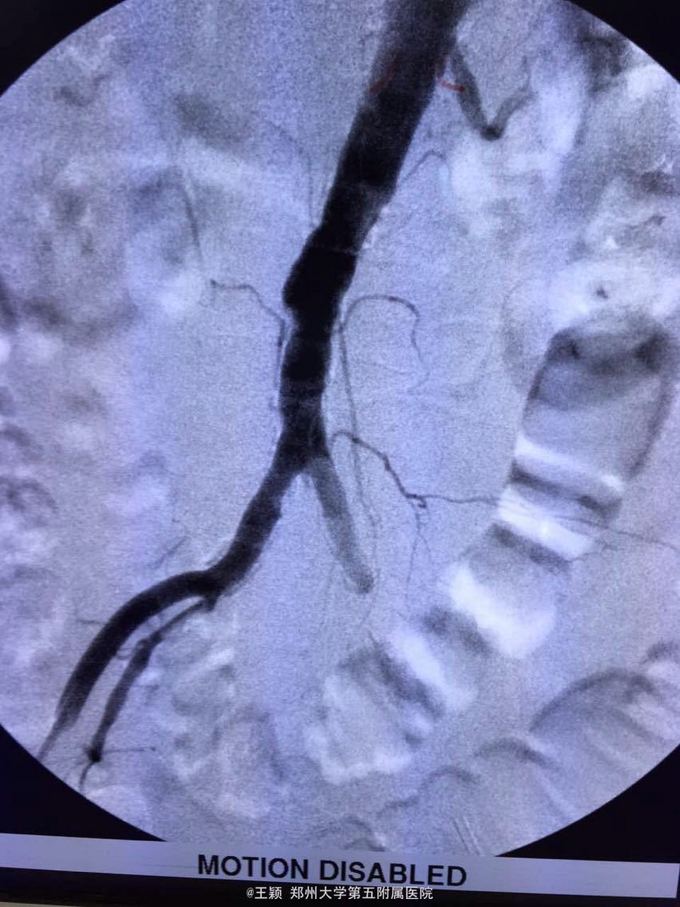

腹主动脉骑跨栓,心律不齐 房颤 急诊全麻下行双股动脉切开去栓及造影术,术后抗凝,解痉,改善循环,营养神经,抗炎,利尿及碱化尿液,监测肾功能,电解质等,随时准备透析治疗